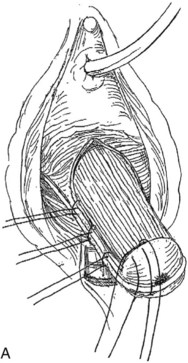

Figure 72–16 Vaginal paravaginal repair. A, Unopened anterior vaginal wall with marking sutures placed at anatomic level of bladder neck and vaginal apex. B, Anterior vaginal wall opened via a midline incision. Sutures placed for midline cystocele repair. C, Midline cystocele repair completed. Bilateral paravaginal defects identified. D, Bladder retracted medially to expose lateral pelvic sidewall. Permanent sutures have been passed through the white line. E, Top two sutures have been passed through detached edge of pubocervical fascia. F, Three-point closure is completed with all sutures passed through the pubocervical fascia and inside wall of the vagina.

(From Mallipeddi PK, Steele AC, Kohli N, et al. Anatomic and functional outcome of vaginal paravaginal repair in the correction of anterior vaginal wall prolapse. Int Urogynecol J 2001;12: 83–88, with permission.)

A midline anterior vertical incision is made through the vaginal epithelium from the bladder neck to the vaginal apex. After the vaginal epithelium is sharply dissected off the attenuated pubocervical fascia and bladder the dissection is carried laterally to the pelvic sidewall. Blunt dissection can be used to facilitate this. Access to the pelvic sidewall is achieved by either continued lateral dissection or perforation of the endopelvic fascia. On entry into the retropubic space, palpation is utilized to identify the ATFP as it courses from the ischial spine to the inferior aspect of the pubic ramus. Deep, lighted retractors may be useful to facilitate exposure. With the bladder retracted medially, five to seven interrupted nonabsorbable sutures are placed at 1-cm intervals through the ATFP. A Capio Suture Capturing Device (Boston Scientific, Natick, MA) may expedite placement of these sutures. These sutures are then passed through the lateral edge of the detached pubocervical fascia. No sutures should be tied until all are placed on either one side or both sides (if bilateral defects). At this point, if indicated, central defect plication sutures may be placed to complete a combined repair. As with anterior colporrhaphy, cystoscopy must be performed to confirm ureteral patency and the absence of intravesical sutures. The vaginal wall is trimmed and closed with a 2-0 absorbable suture. Vaginal packing is placed.